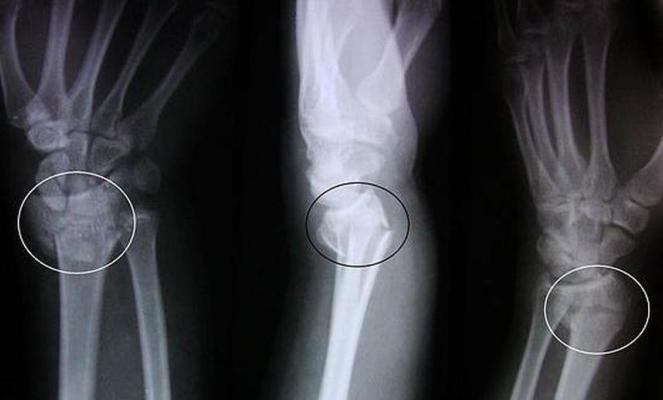

Ученые под руководством Эндрю Ына завершили работу над одним из своих самых амбициозных проектов – MURA. Это база данных, включающая в себя более 40 000 рентгеновских снимков поврежденных конечностей с разметкой радиобиологов. Искусственный интеллект обучался при работе с базой снимков повреждений, отмеченных как «нормальное» или «патологическое».

Во время контрольного теста эффективность работы нейросети сравнивали с показателями трех профессиональных радиологов. В результате нейросеть превзошла людей, поставив точные диагнозы в 74,9% случаев, передают «Новости без границ».